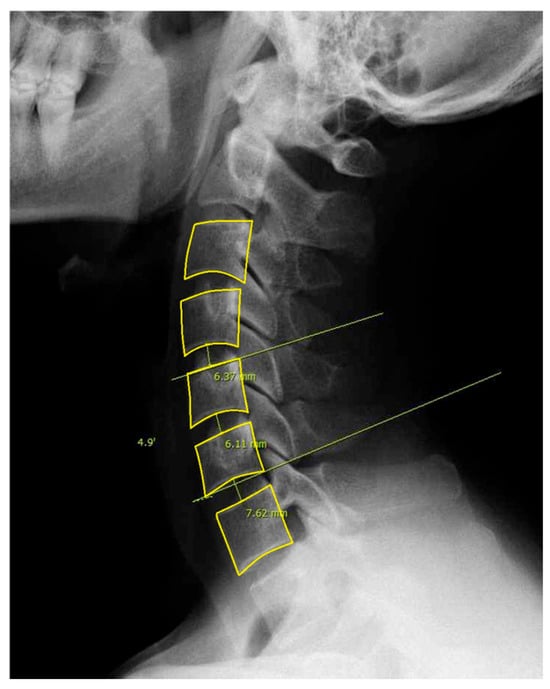

For this study, we included patients with labeled DCM and utilized pre-labeled cervical lateral radiographs (Figure 1). Specifically, annotations included the following: (1) Identification and marking of anatomical landmarks (key points) on the cervical vertebral bodies (C3–C7). (2) Measurement of cervical sagittal parameters such as cervical lordosis, sagittal vertical axis (SVA), vertical length, and curved length. (3) Calculation and labeling of intervertebral angles and vertebral disk heights. (4) Polygon-based segmentation is used to accurately delineate the cervical vertebral region. All eligible lateral cervical radiographs were included in this study. As unsupervised clustering does not require predefined groupings, we used the full dataset to ensure the robustness and generalizability of the clustering results.

Figure 1. Example of labeled lateral cervical spine radiographs used in this study. The dataset includes segmentation and labeling of the vertebral bodies from C3 to C7.